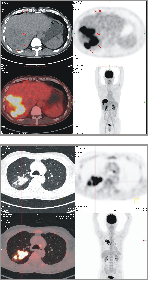

1、PET/CT肿瘤显像

·全身各种肿瘤早期诊断、分期,以及良恶性鉴别,评价肿瘤恶性程度,指导制定最佳治疗方案

·判断肿瘤术前、术后有无转移,评价肿瘤治疗效果,以及肿瘤对放、化疗的反应

·鉴别肿瘤复发或治疗后坏死、纤维化

·为不明原因的转移性肿瘤和肿瘤标志物升高寻找原发病灶

·放疗前确定肿瘤病灶的生物靶区,准备区分肿瘤组织与正常组织,提高放疗疗效、降低放疗副作用

·指导肿瘤穿刺活检、选择最佳活检部位、提高活检确诊率